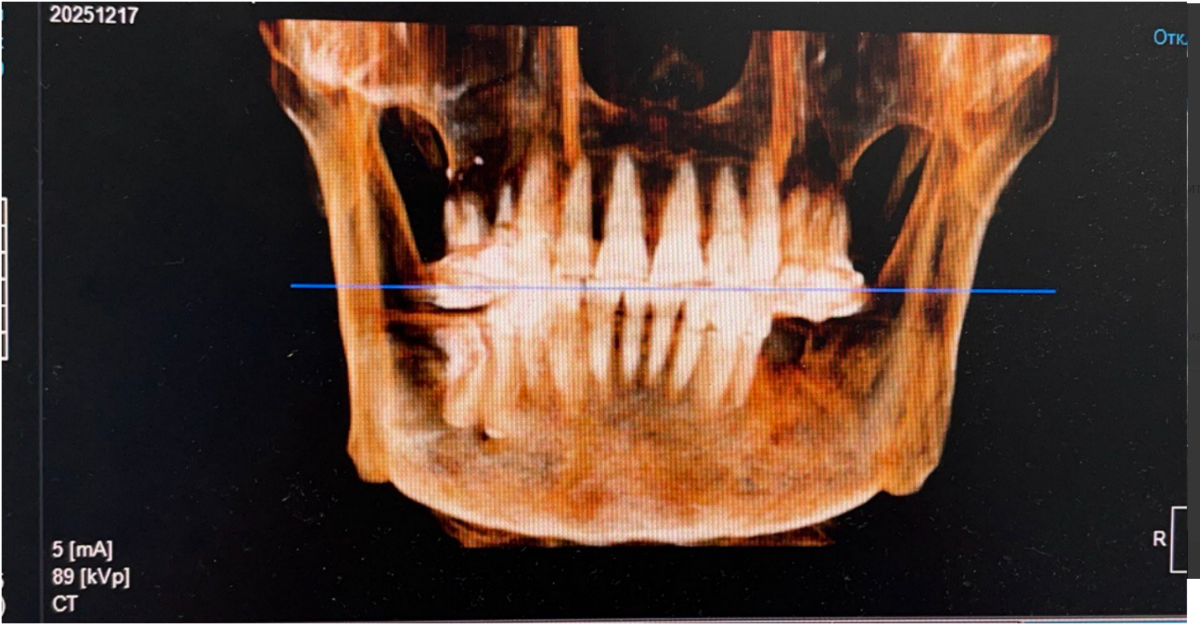

Женщина 74 года. Установила бюгельный протез на нижнюю челюсть 2 года назад, который крепится справа на коронке с замком, а слева на заглушенных имплантатах. Имплантатам свыше 15 лет, на консультациях сказали, что их больше нельзя использовать для протезирования, кость плохая, только удаление. Ортопед принял решение имплантаты не удалять, а использовать их в систему для бюгельного протеза. Недавно под протезом стал побаливать зуб при надкусывании. Сделала КТ. Справа на зубе под коронкой с замком, на котором держится эта конструкция, образовалась гранулема. Теперь встал вопрос: как быть. Почему образовалась гранулема? До протезирования ничего не было, могла такая конструкция вызвать воспаление? Можно ли вылечить данный зуб? В клинике, где делали КТ, предложили, как вариант, высверлить в коронке дырку и попытаться пролечить зуб.  Поможет ли это? Или снимать коронку, как полагается, и лечить классическим методом? Что можно сделать в данном случае? Или уже ничего не поможет? Оставить всё как есть до тех пор, пока зуб окончательно не разболится и просто его удалить?